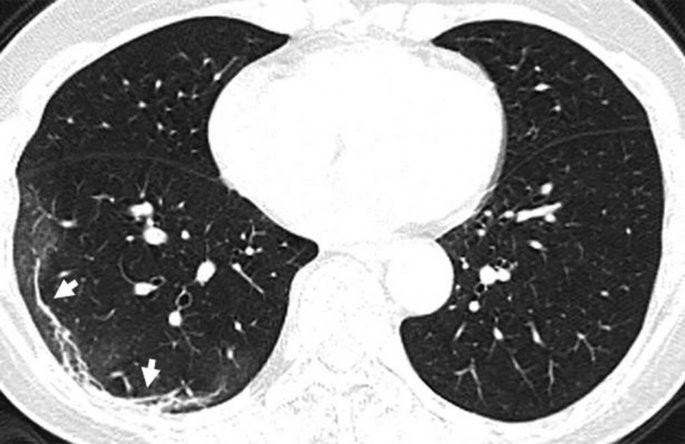

Κορωνοϊός: Ανατριχιαστική ακτινογραφία ασθενούς